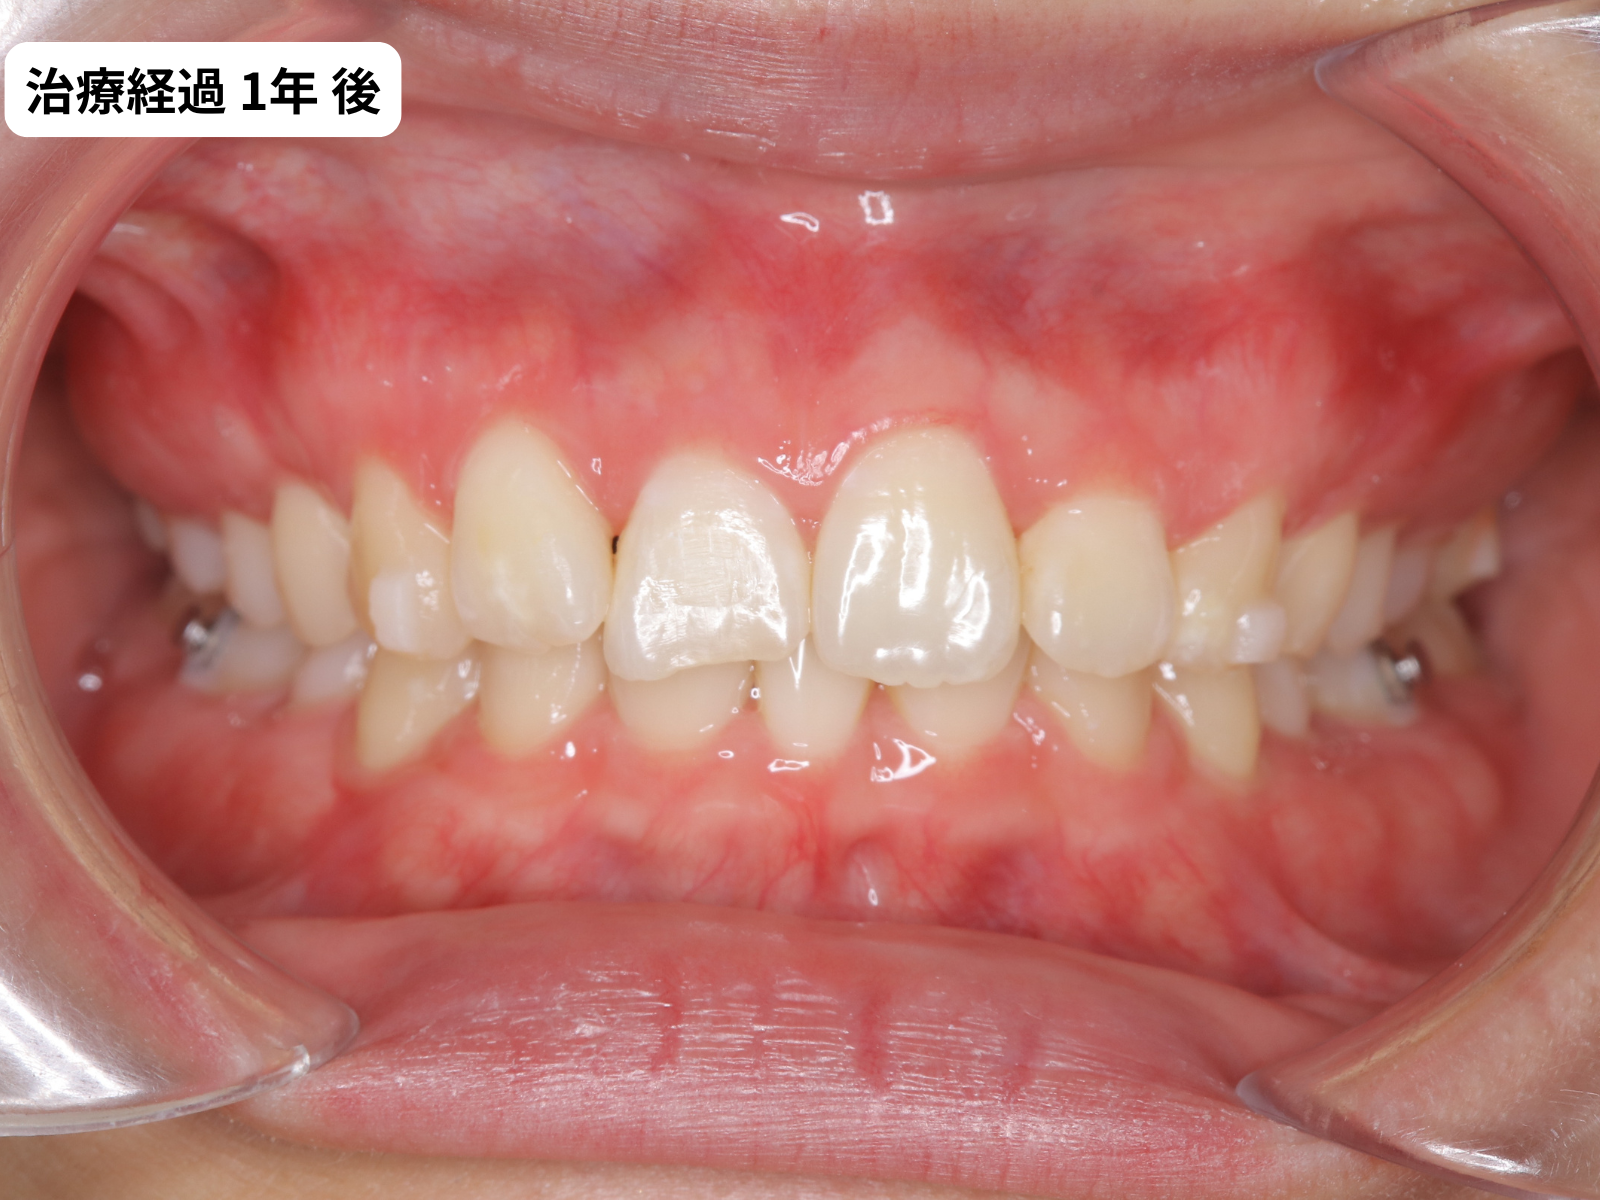

過蓋咬合が改善していく経過(正面)

過蓋咬合の変化が一番分かりやすいのは正面の噛み合わせ写真です。下の前歯がだんだん見えるようになっていく経過をご覧ください。

1年 矯正治療1年目の正面|過蓋咬合改善経過|奈良の矯正歯科

正面写真で見ると、下の前歯がだんだん見えるようになっていくのが分かります。これが過蓋咬合の改善です。マウスピース矯正でも、軽度であれば奥歯のわずかな挺出と前歯の調整でしっかり改善できます。